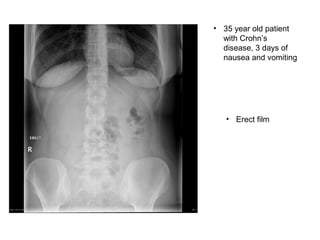

• 35 year old patient

with Crohn’s

disease, 3 days of

nausea and vomiting

• Erect film

• 35 yearold patient with Crohn’s disease, 3 days of nausea and vomiting • Erect film